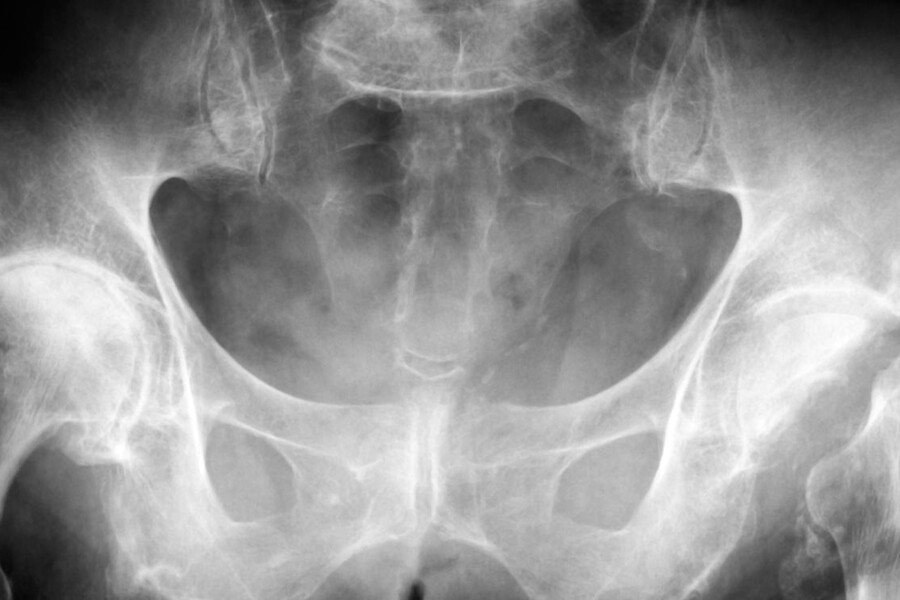

Leggova nemoc je forma avaskulární nekrózy hlavice kosti kyčelní, kdy stehenní kost dítěte (femur) přestane být zásobována krví a horní konec kosti během 1 až 3 týdnů odumírá. Zásobování krví může být přerušeno v důsledku náhodného úderu do kosti, infekce nebo je příčina neznámá. Zásobování krví se během 6 až 12 měsíců po zranění obnoví a během 2 až 3 let je odumřelá kost nahrazena novou.

Leggova nemoc se vyskytuje nejčastěji u chlapců ve věku 3 až 10 let. Obvykle je postižena pouze jedna dolní končetina. Asi v 10% případů jsou však zasaženy končetiny obě.

Má-li dítě příznaky Leggovy nemoci, lékař zjistí, jak dítě chodí a stojí a v jakém rozsahu může pohybovat kyčlemi. Diagnózu určí na základě rentgenového a radionuklidového vyšetření a pravděpodobně pošle dítě k ortopedovi. Vzhledem k tomu, že si tělo dítěte obvykle pomůže samo, lékař bude pouze chránit končetinu před dalším zraněním a stresem, dokud se sama nezahojí. Doporučí dítěti, aby nohu co nejméně zatěžovalo a hlavně zpočátku ji udržovalo v klidu. Připevní na postiženou nohu ortézu, která ji bude udržovat ve správné poloze. Některé děti budou muset prvních několik dní podstoupit trakci a pak dostanou ortézu. U těžkých forem této nemoci bývá nutná operace.